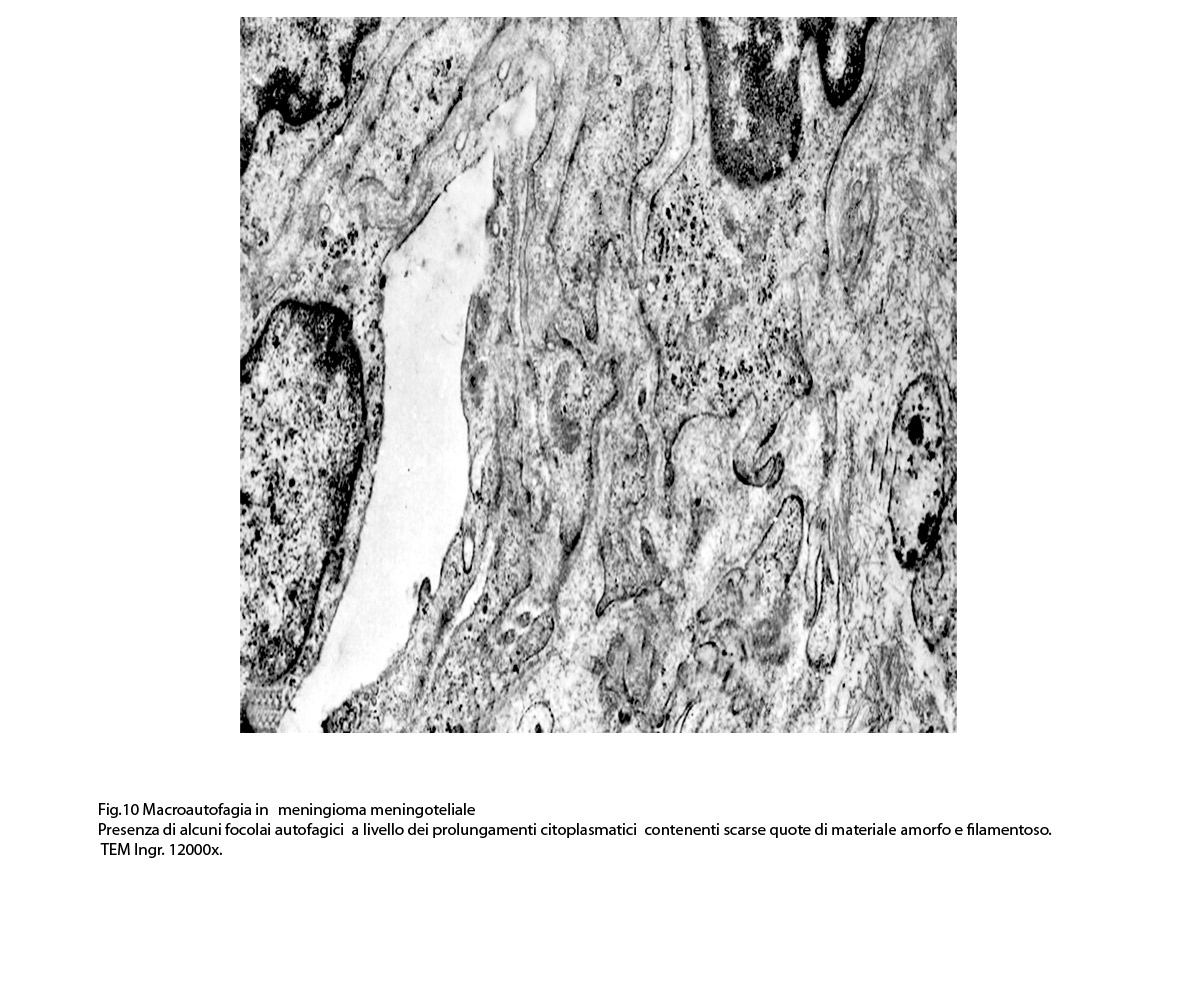

I focolai di macroautofagia possono essere presenti in zone diverse del citoplasma. La loro microstruttura di base è costituita da una area vacuolare demarcata da una membrana a doppio strato; l’area cava è occupata per quote variabili da materiale amorfo,da aggregati filamentosi,da frammenti di organuli,da gruppi granulosi, il tutto in diversi stati di conservazione. Questi focolai macroautofagici appaiono come strutture avulse dalle mutevoli condizioni bio-morfologiche del citoplasma nel quale si sono formate. E’ frequente il riscontro di cellule di aspetto cribroso per la esistenza di micro vacuoli scavati nel citosol e per la dilatazione delle cisterne del reticolo endoplasmico contengano nel citosol una formazione macroautofagica occupata in parte da materiale amorfo e filamentoso.

Non mancano elementi cellulari,forniti di un citosol contenente solo ribosomi liberi, rare strutture reticolo endoplasmatiche in via di disgregazione e molto materiale amorfo, essere occupati da un focolaio di macroautofagia con aggregati di filamenti.

Sono repertabili anche cellule meningoteliali ben strutturate e ricche di organuli marcate da un focolaio di autofagia contenente frammenti di substrutture e materiale filamentoso.

Anche a livello di prolungamenti citoplasmatici di cellule meningoteliali si riscontra la presenza di due focolai autofagici occupati in parte da materiale amorfo.